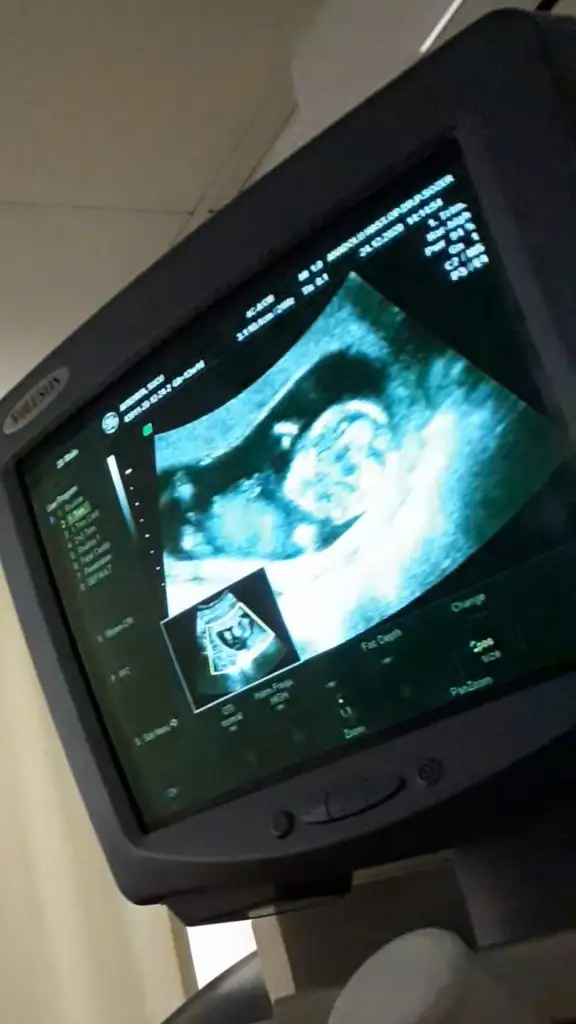

Cinsiyet tahmini yapabilir misiniz :) 9+5